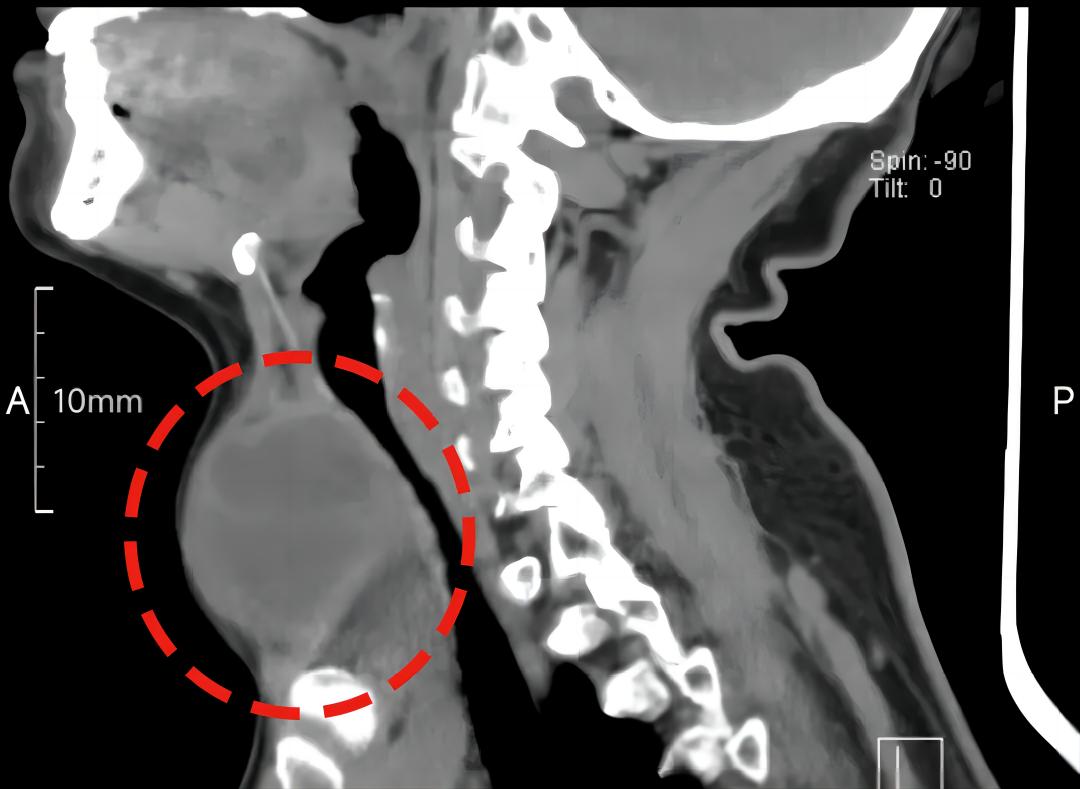

近日,我院乳腺甲状腺外科为一位患者成功切除了12cm的甲状腺肿物。

12cm!火龙果一样大的甲状腺肿物,很难想象她每日呼吸是多么困难。

王民开带领科室团队制定了周密的手术方案。他们反复查看患者影像资料,评估肿块与周边重要结构的关系,脑中不断模拟术中可能出现的场景,明确了肿块的可切除性,力求在保护喉返神经、甲状旁腺等重要组织器官的同时,彻底切除病灶。

结合巨大甲状腺肿物位置及大小,为手术和麻醉插管都带来了一定的挑战。